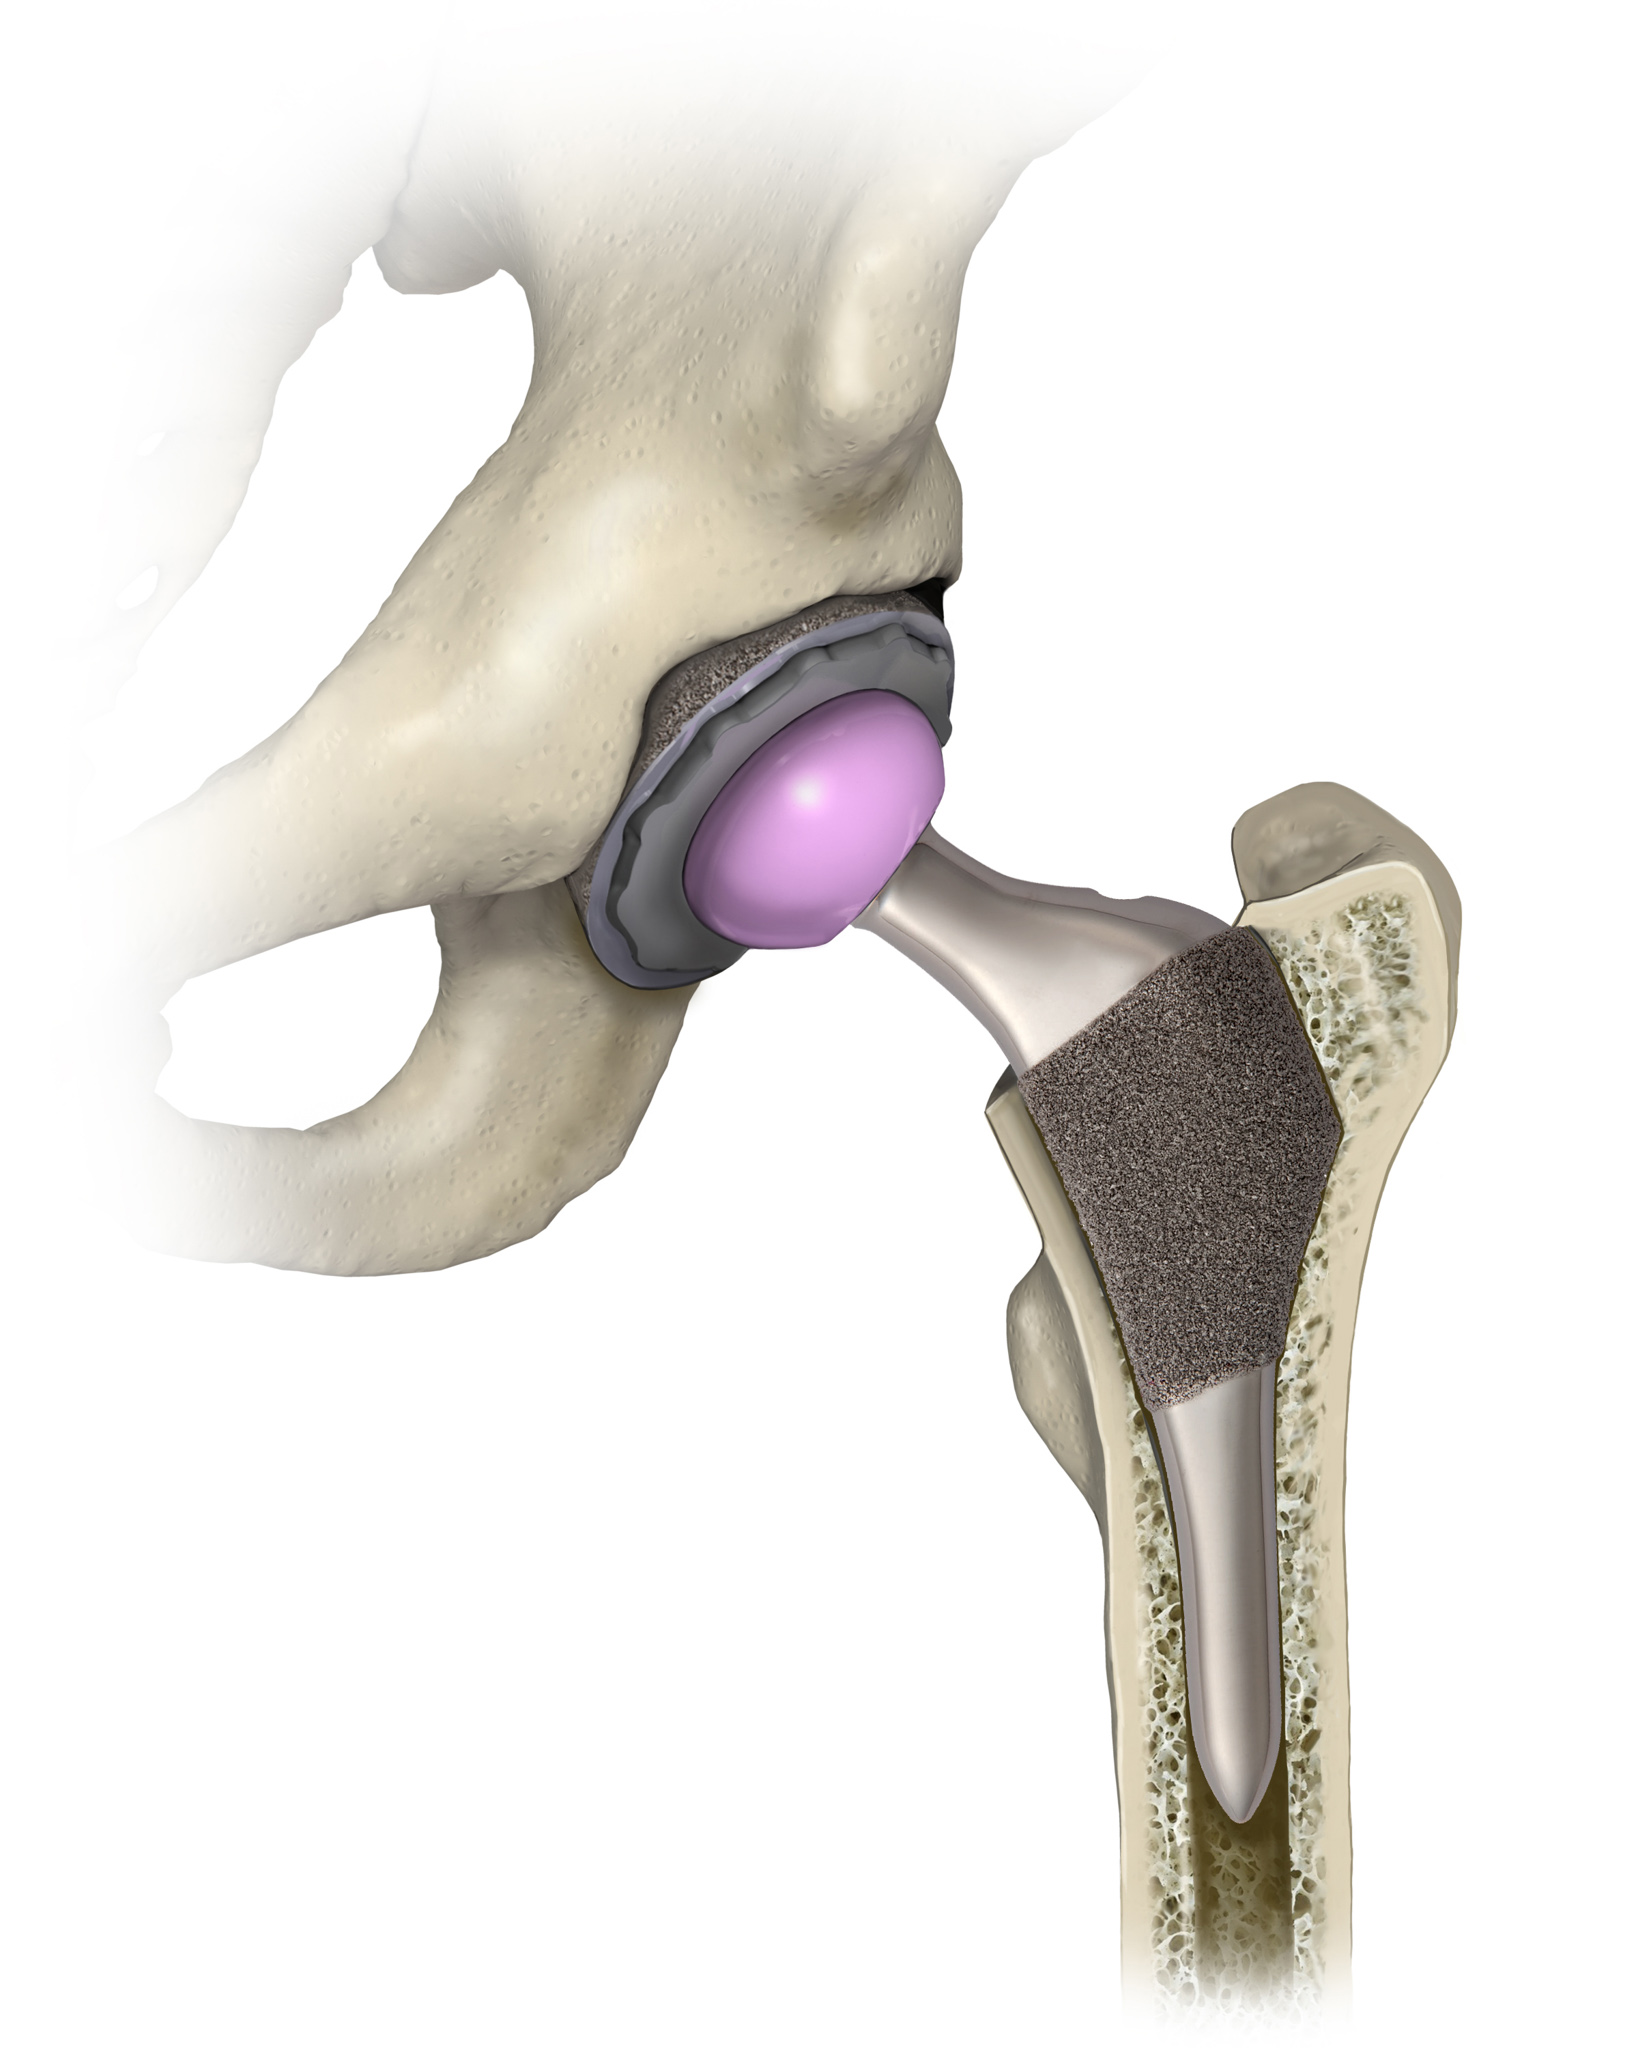

I create medical illustrations, animations, interactive projects and timelines for physicians, attorneys, medical device and pharmaceutical companies to create illustrations for educational purposes.

I work a lot with attorneys to create medical demonstrative aids for insurance adjusters, mediations and trials. These medical demonstratives help to secure settlements for severely injured and families of decedents.

I am proud to educate people. To scientifically visualize what’s unseen by the naked eye for the general public!